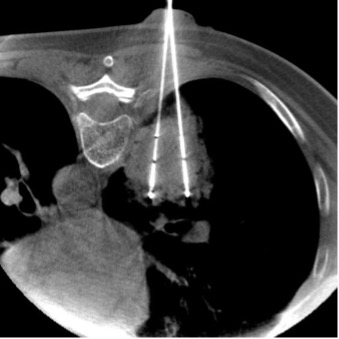

Стандартный рабочий процесс начинается с выполнения ПДКТ без контраста (например, для биопсии или абляции опухолей легких) или с использованием внутриартериального (например, для абляции узлов ГЦР в печени), внутривенного (например, для проведения крионейролизиса), эндолимфатического или других видов контрастирования (рис. 14). Далее на рабочей станции выполняется полуавтоматическая или автоматическая сегментация (выделение) целевых и критически важных структур, а также интерактивное построение безопасной траектории чрескожного таргетирования путем установки двух точек, одна из которых располагается в целевой зоне, а вторая – в точке входа аппликатора на коже. Далее, в автоматическом режиме, осуществляется построение трассы таргетирования и после оценки ее безопасности (избегание крупных сосудисто-нервных пучков, полых органов и др.) она регистрируется в стереотаксическом пространстве («геометрии») С-дуги таким образом, что 3D-карта накладывается на рентгеноскопическое изображение и обновляется вместе с изменением положения гентри, что позволяет совмещать иглу или аппликатор с прогнозируемой целью в режиме реального времени [62, 66]. Дополнительные опции наведения иглы, такие как захват цели, подсвечивание ортогональных (взаимно-перпендикулярных) проекций с помощью лазера, информирование врача о глубине установки аппликатора, предназначены для уменьшения числа ошибок и очень помогают при таргетировании с использованием сложных углов атаки, а также в случаях «длинных траекторий», проходящих через подвижные органы (рис. 15). При проведении энергетической абляции, биопсии и других чрескожных вмешательств после установки иглы или аппликатора в целевую область обязательно проводится повторное ПДКТ-сканирование для подтверждения адекватного расположения устройства в целевой зоне. Ранее было показано, что использование технологий чрескожной стереотаксической навигации значительно облегчает проведение чрескожных вмешательств, в особенности при таргетировании образований диаметром менее 10 мм, не визуализируемых при УЗИ, повышая техническую эффективность и безопасность ряда процедур, в частности чрескожной биопсии опухолей легких [18, 64]. Более того, выполнение различных чрескожных рентгенохирургических вмешательств (биопсия, дренирование, абляция и т.д.) под ПДКТ-контролем осуществляется значительно быстрее, точнее и технически более эффективно по сравнению с выполнением тех же вмешательств под контролем МСКТ, при этом эффективная доза облучения на 13-42% меньше [68-71].

Рис. 15. Введение антенны для микроволновой абляции в опухоль печени под контролем ПДКТ с использованием штатной лазерной подсветки ангиографического комплекса Artis Zee (Siemens Healthineers, Германия): после выполнения ПДКТ-артериогепатикографии и определения безопасной траектории таргетирования С-дуга ангиографической установки устанавливается в положение «вид сверху», после чего автоматически включается лазерная подсветка, позволяющая без использования рентгеноскопии определить точку входа аппликатора на коже пациента; при правильном расположении аппликатора, согласно запланированной траектории таргетирования, визуализируется лазерная подсветка на всем протяжении шафта антенны для микроволновой абляции в двух взаимно-перпендикулярных проекциях, что позволяет без включения рентгеноскопии точно провести аппликатор в тело пациента на заранее определенную глубину.